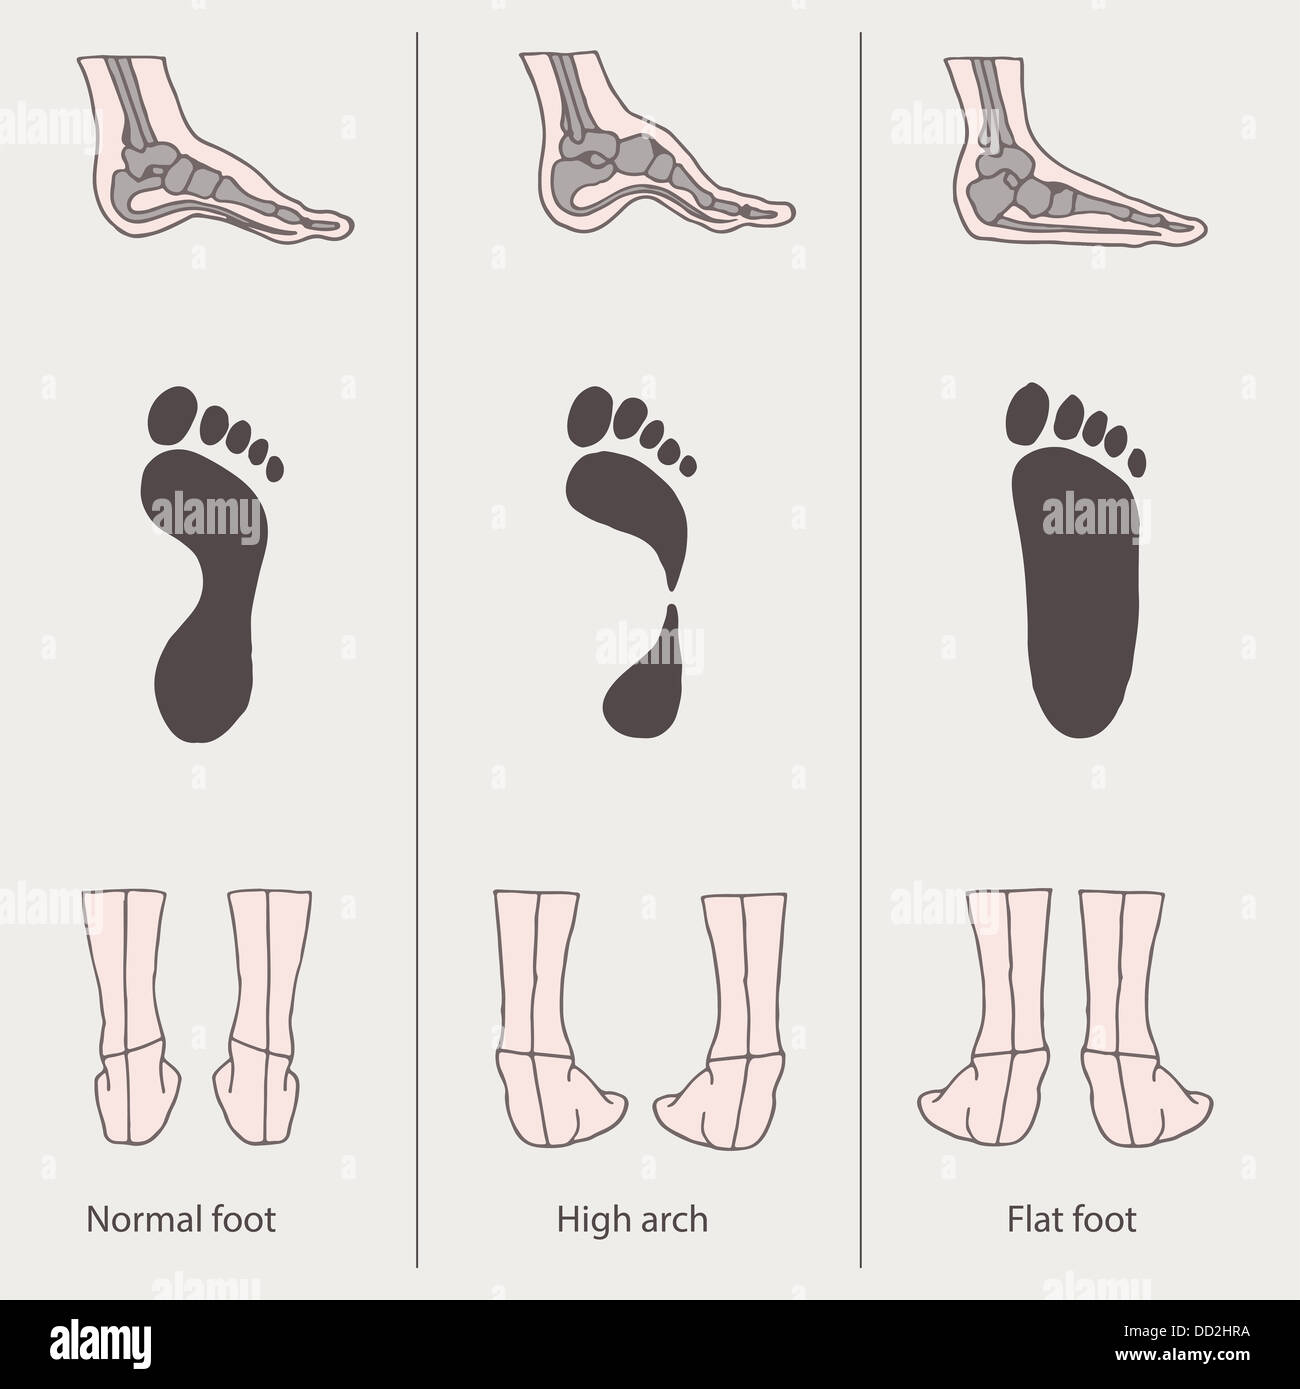

Foot Postures: What It Means for Your Feet?

Flat Feet and High Arched Feet | Things to Know – Custom Rehab

Understanding Foot Types and Managing the Adolescent Athlete